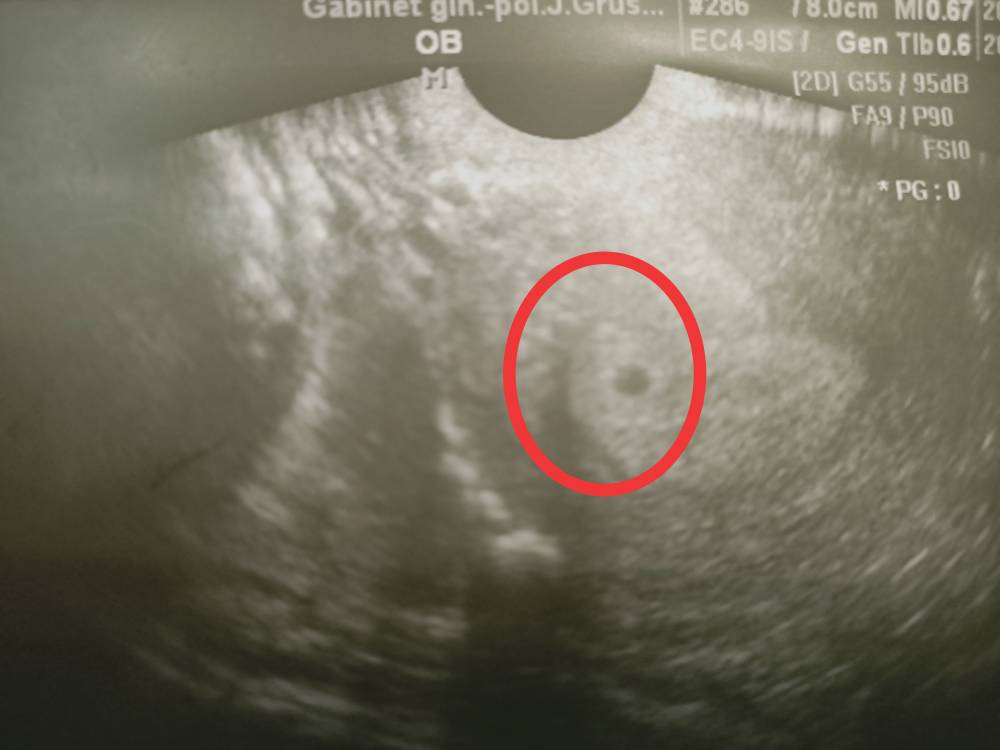

Jest pęcherzyk. [emoji4] Kolejna wizyta 16.11.

A tu poniżej przedstawiam swój pęcherzyk.Zobacz załącznik 1197211Zobacz załącznik 1197212